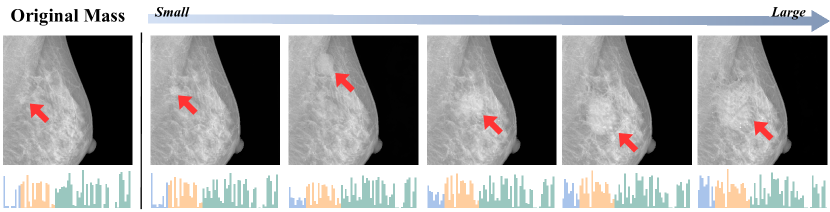

Fig. 5 showcases synthetic tumors generated with progressively increasing the shape feature of size, while other features remain constant. This visualization demonstrates our model’s ability to adapt to specific tumor characteristics, illustrating the potential for generating diverse, tailored synthetic tumors based on specific condition prompts.

Refer to caption

Figure 5: Progressive Shape Variation in Synthetic Tumors. Starting with an image containing a mass, we use a normal prompt to replace the mass area with normal tissue. Then, at random positions, we generate synthetic tumors of increasing size, keeping histogram and texture features consistent. Red arrows in each image point to the mass. Below each image, histograms display the radiomics features extracted from the tumor areas.